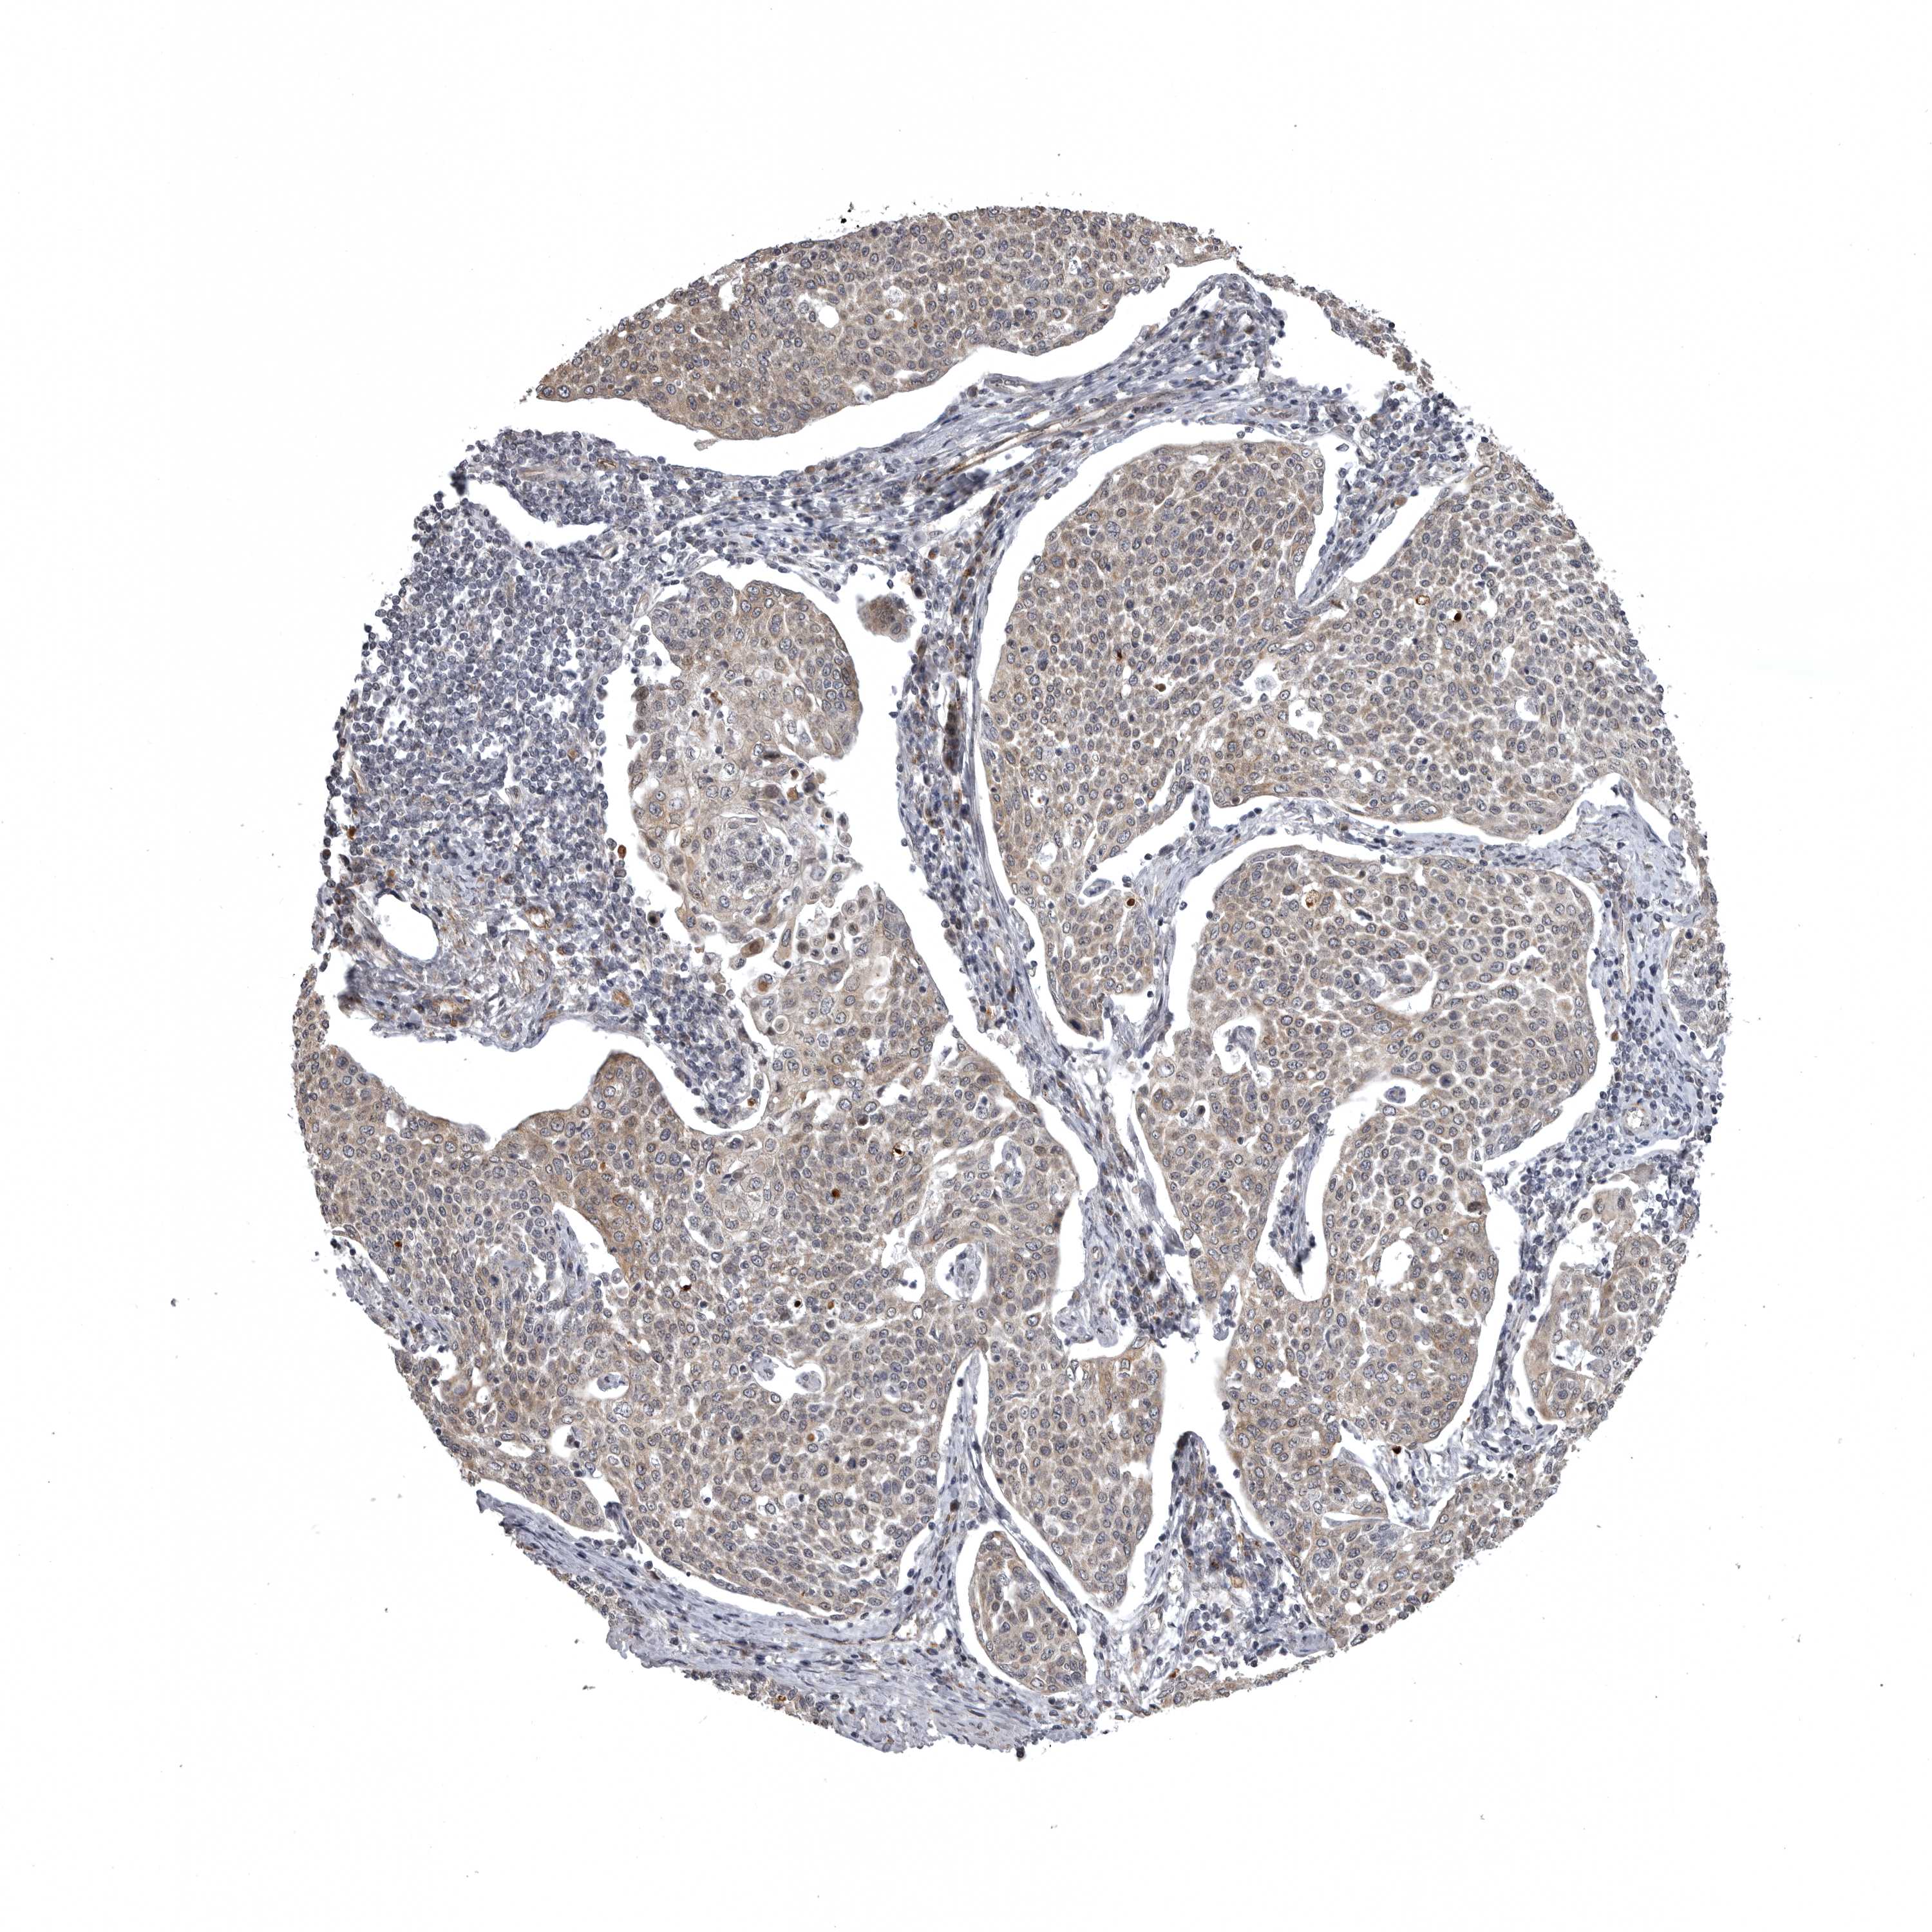

CERVICAL CANCER - Protein expressioni

A mouse-over function shows sample information and annotation data. Click on an image to view it in a full screen mode. Samples can be filtered based on level of antibody staining by selecting one or several of the following categories: high, medium, low and not detected. The assay and annotation is described here.

Note that samples used for immunohistochemistry by the Human Protein Atlas do not correspond to samples in the TCGA dataset.

Antibody stainingi

Antibody staining in the annotated cell types in the current human tissue is reported as not detected, low, medium, or high, based on conventional immunohistochemistry profiling in selected tissues. This score is based on the combination of the staining intensity and fraction of stained cells.

Each image is clickable and will lead to virtual microscopy that enables deeper exploration of all samples and also displays staining intensity scores, fraction scores and subcellular localization as well as patient and tissue information for each sample.

Antibody HPA024730

Antibody HPA024731

Squamous cell carcinoma, NOS

Adenocarcinoma, NOS